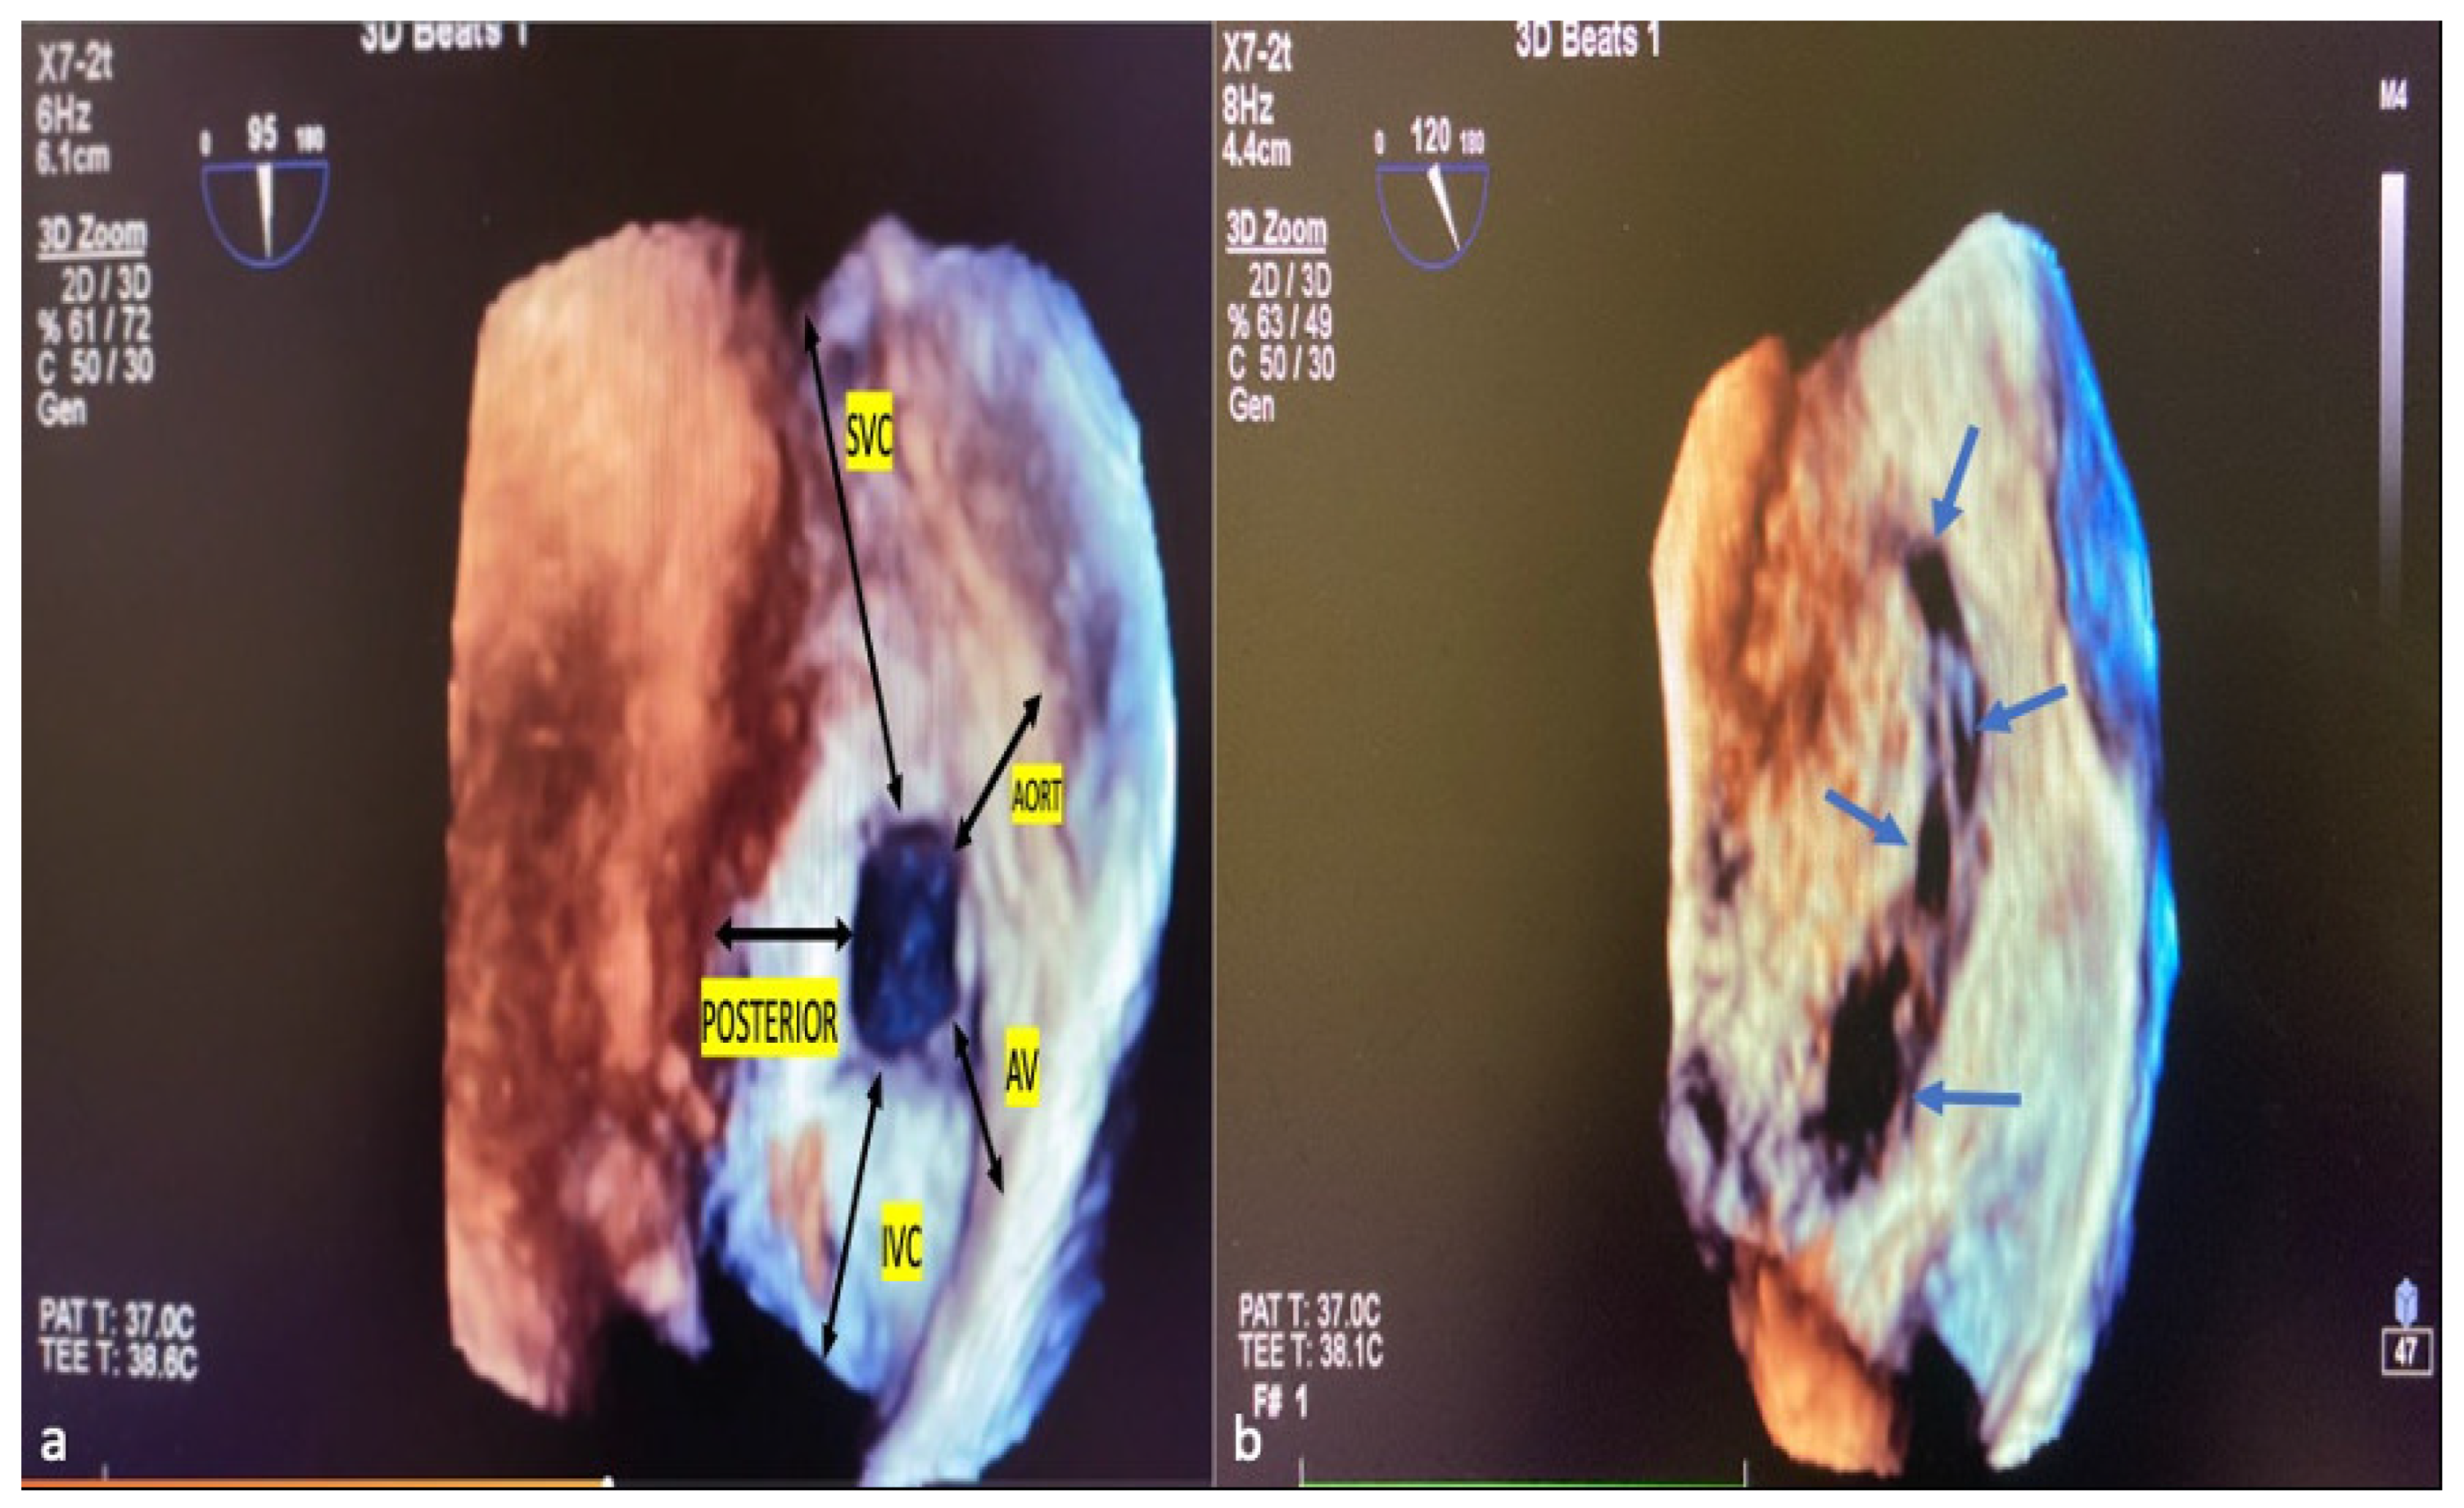

ASD residual rims: This is defined as the distance between the edges of the ASD and the surrounding intact atrial septum tissue. ASD residual rims were examined in detail by slicing or cropping 3D full-volume and 3D zoom datasets. The maximum rim length was based on the value measured at the end of the systole. The superior or inferior residual rim was determined by the distance from the defect edge to the SVC or IVC in the mid-to-high esophageal position. The posterior rim was measured as the distance between the defect edge and the posterior wall. The antero–superior (aortic) residual tissue rim is the distance between the defect edge and the aortic wall in the mid–upper esophagus position in the short axis. The antero–inferior residual rim (AV valve rim) is the distance between the ASD border and the atrioventricular valve annulus in the mid-esophageal 4-chamber view. ASD morphology: From the en-face view, when the minimum diameter was equal to or greater than 75% of the maximum diameter, it was considered a circular defect, and when it was smaller, it was considered an elliptical or oval defect [21]. Complex ASDs were defined according to their shape and/or location. The ASDs are considered complex if the defects are large (>26 mm), have deficient septal rims (particularly inferior rim), atrial septal aneurysm is present, or defects are multiple or fenestrated [22]. Figure 4a,b show the ASD rims defined, respectively, and a multi-fenestrated ASD example.

Figure 4. ASD rims and multi-fenestrated ASD image in 3D TEE. The tissue lengths indicated by black arrows in the RA (a), en face view, describe the ASD rims. Example of complex, multi-fenestrated ASD (Blue arrows) (b). SVC, superior vena cava; AV, atrioventricular; IVC, inferior vena cava; POSTERIOR, posterior rim; AORT, aortic rim.